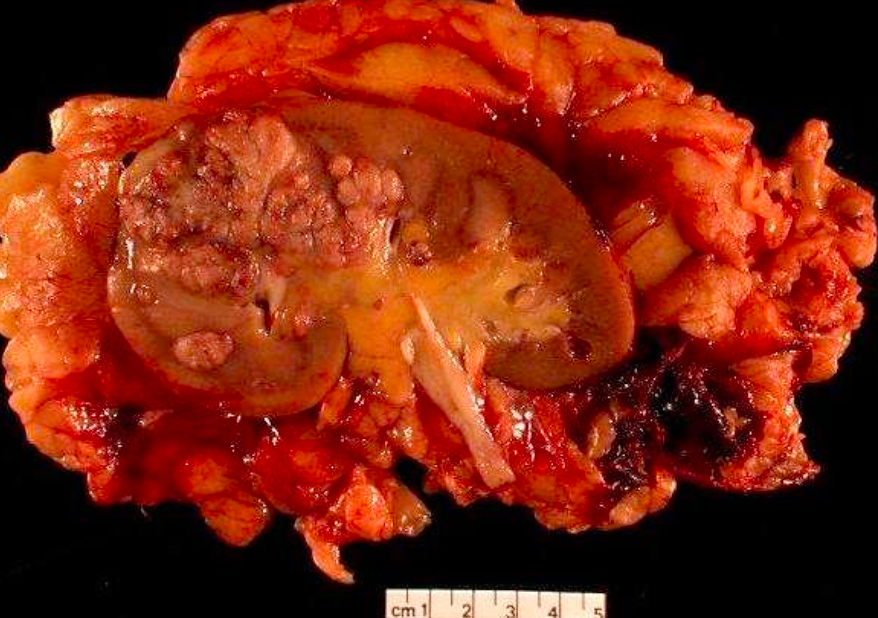

65세 남자가 왼쪽 옆구리 통증과 혈뇨로 병원에 왔다. 영상의학 검사에서 콩팥종양이 의심되어 바늘 생검 후 신장적출술을 받았다. 육안 및 현미경 사진이다. 이 종양의 발생과 관련 있는 유전자는?

[유두상 신세포암, Papillary renal cell carcinoma]

• 적출된 신장과 조직사진은 papillary renal cell carcinoma를 시사한다.

• Papillary carcinoma는 전체 신장암의 10-15%를 차지하며 cuboidal 또는 low columnar cell 로 이루어진 papillary growth pattern을 보인다. 이외로도 foam cell(=지방을 함유하는 macrophage)을 다수 관찰할 수 있다.

• 지문에서 주어진 사진에서는 보이지 않지만, psammoma bodies(=calcium stone)도 흔하게 관찰된다.

• Papillary carcinoma는 보통 multifocal, bilateral하게 나타나며 hemorrhagic 그리고 cystic하다.

• Papillary carcinoma의 대부분은 sporadic하지만 일부는 가족성으로 나타나기도 한다. 그 중 Hereditary papillary renal cell carcinoma는 7번 염색체에 존재하는 proto-oncogene인 MET의 돌연변이와 연관성을 보인다. MET는 hepatocyte growth factor의 tyrosine kinase receptor의 유전자이다.